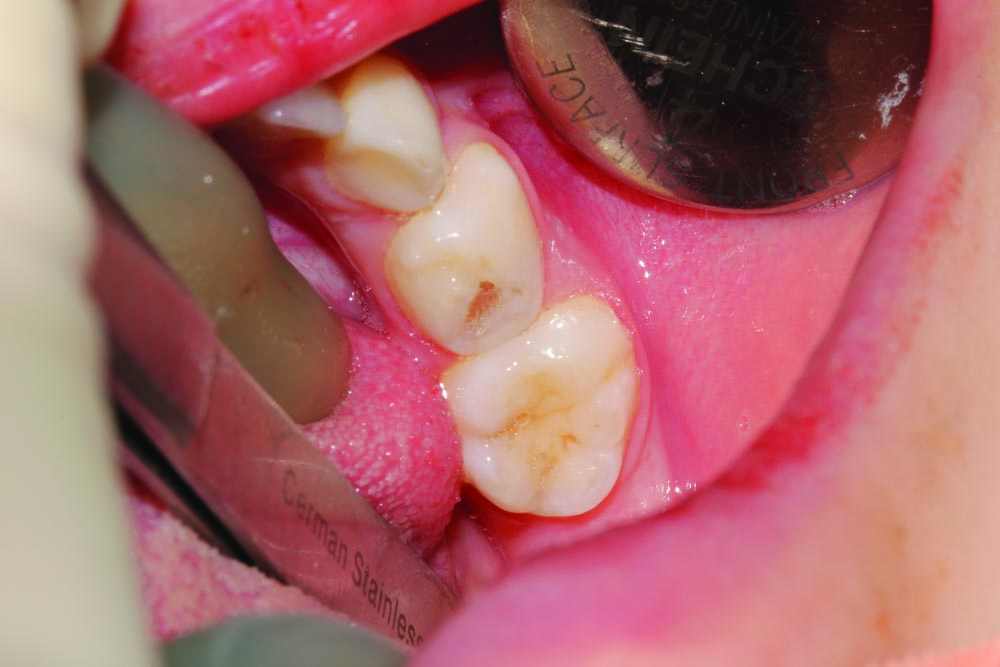

A shy and apprehensive 3-year-old female patient presented with multiple caries in all quadrants. To keep the patient's in-office experience positive, all posterior teeth were restored with a combination of atraumatic restorative techniques and minimally invasive techniques.

Maxillary anterior incisors #52–#62 (D–G) all exhibited varying depths of decay and required restoration (Fig. 6). Only topical anesthetic was used, and the area was isolated with cotton rolls. Teeth were minimally prepared into enamel only with an NSK high-speed handpiece and a tapered rough grit diamond FG bur.

Caries was excavated with a spoon excavator (Fig. 7). Because isolation was a challenge, all surfaces of affected teeth were bonded with a self-etch procedure using Futurabond U and then light-cured (Fig. 8). Celluloid strip crowns were fitted and vented, filled with GrandioSO by Voco, seated and light-cured.

Celluloid strips were removed and composite strip crowns were polished with Enhance polishing cups by Dentsply. Final restorations are functional and aesthetic (Fig. 9). Because of the process of minimally invasive technique and adaptable materials, it was possible to carry out this procedure in office without local anesthetic, resulting in a successful restorative outcome and a positive patient experience.

• Figure 7